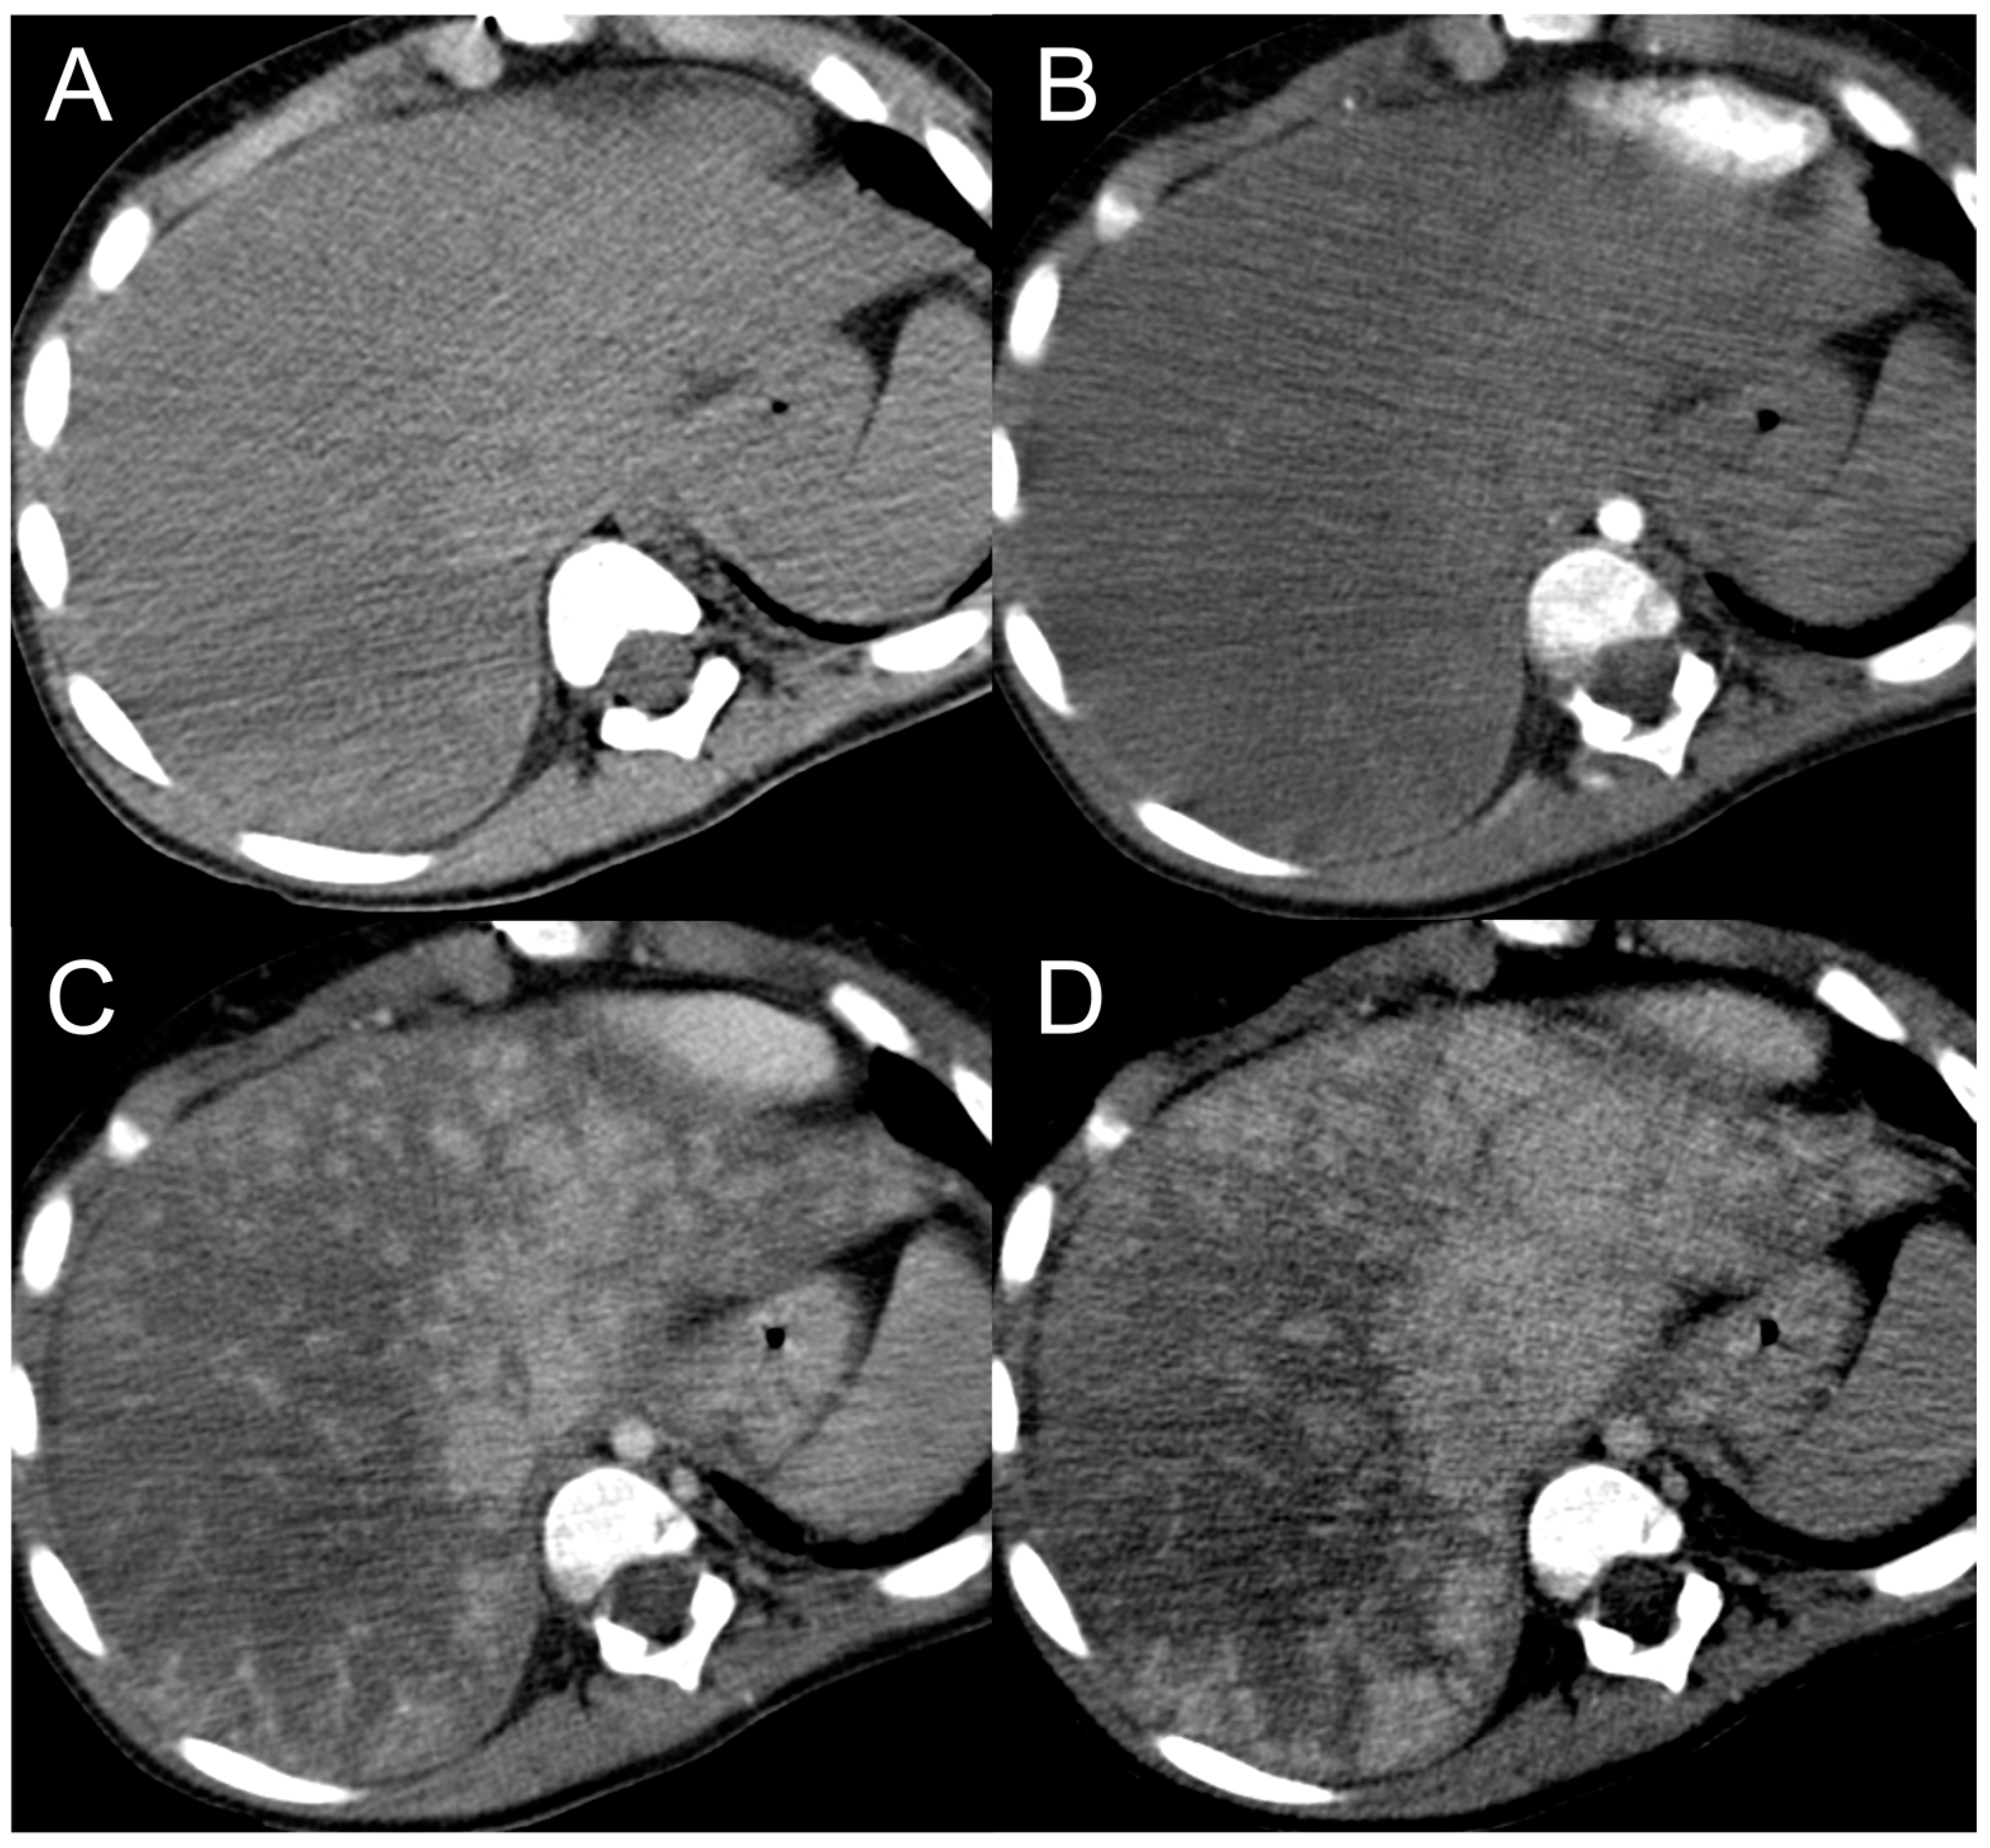

Being composed of nearly normal hepatocytes, >95% of FNH-like RNs are isodense to surrounding parenchyma on nonenhanced CT imaging (Figure 1A) [14]. In some cases, when located in the subcapsular region, they may be detected due to the alteration of liver contours. More rarely, they may appear hyperdense or hypodense compared to the liver.

Figure 1.

CT examination of 36-years-old male patient with Budd–Chiari syndrome. On unenhanced images (A), the liver parenchyma appears relatively homogeneous, and the presence of TIPS stent (arrowhead) and perihepatic ascites (asterisks) can be observed. On arterial phase (B), multiple homogeneously enhancing FNH-like RNs can be visualized in the liver (arrows), some exhibiting a hypodense perinodular rim (arrowhead) due to atrophic hepatic tissue with congested sinusoids. In both portal venous (C) and delayed phase (D), the regenerative nodules (arrows) become iso-dense or slightly hyperdense compared to the surrounding inhomogeneous liver parenchyma, making them difficult to detect.

After iodine contrast administration, the nodules are well evident on arterial phase images because they are hypervascularized, hence showing marked and homogeneous contrast enhancement in almost all cases (Figure 1B). Hypervascularization is atypical in cirrhotic regenerative nodules, but in FNH-like RNs associated with BCS it probably represents a compensatory response to regional loss of portal flow. On the portal and late venous phases, the FNH-like RNs usually remain isodense or slightly hyperdense (Figure 1C,D). A hypodense perinodular rim may also be observed on contrast enhanced CT imaging because of the presence of atrophic hepatic tissue around the nodule with sinusoidal congestion.